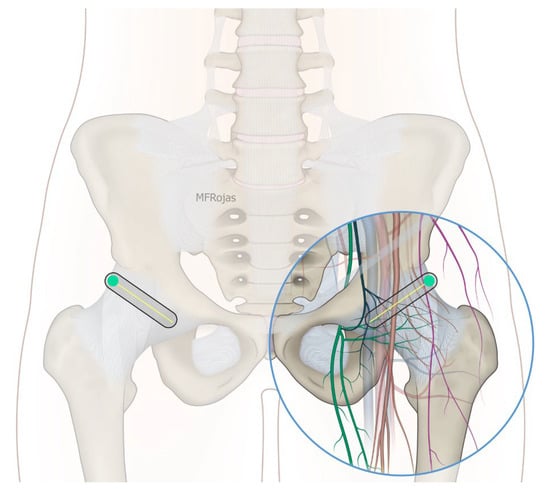

The growing impact of fragility hip fracture on the healthcare system and on society has become a major concern worldwide. Despite the advances in perioperative medicine and anaesthetic care, a minority of frail patients are still too ill to be surgical candidates. Hip fracture analgesia generally includes non-pharmacological modalities, oral and injectable analgesics, traction and regional nerve block [1,2]. However, given the complexity of medical comorbidities in this patient population, pain management of hip fracture is not a one-size-fits-all recipe [1]. Acupuncture, relaxation therapy, and transcutaneous electrical nerve stimulation (TENS) may be associated with potentially clinically meaningful benefits, but no firm conclusion can be drawn from the current evidence [1]. Comorbidities may also prohibit the use of these therapies, for instance, pacemakers and anticoagulants. Simple non-opioid analgesics are often insufficient to treat dynamic pain adequately, whereas opioid analgesics can cause disturbing side effects in this patient population, such as dizziness, nausea and vomiting, sedation and even respiratory depression. Traction does not reduce the intensity of acute pain, and patients also remain bed-ridden during this treatment [2]. Regional nerve blocks, such as Pericapsular Nerve Group (PENG) block, fascia iliaca block and femoral nerve block, can effectively manage fracture pain, especially if a catheter is inserted [1,2,3]. Nevertheless, the benefit from a single shot regional nerve block can usually last for 1 to 3 days whilst there is an infective concern if a block catheter is placed for weeks. Community management of the catheter is also a practical concern in our locality. Partial hip denervation hence becomes a treatment option to provide long-lasting analgesia by a single intervention. With the sophistication of ultrasound technology coupled with a greater understanding of hip joint innervations in recent cadaveric studies (Figure 1), there has since been a venture to develop an ultrasound-guided approach to denervate the hip joint. The first such approach was described by Sasaki et al. in 2018 [4], where alcohol was infiltrated superficially over the ligaments encasing the anterior hip joint, namely the iliofemoral and pubofemoral ligaments. Subsequent to our case series demonstrating the efficacy of the conventional approach, which consisted of a PENG injection and an oblique approach to the obturator nerve articular branches (ONAB) [5], we noticed there were circumstances in which the conventional approach did not work well, and enormous technical difficulties were encountered in terms of needle trajectory.

Figure 1. Nerves supplying the hip joint and their relationship to the femoral vessels. Reproduced with permission from Dr Maria Fernanda Rojas Gomez (Bucaramanga, Colombia).